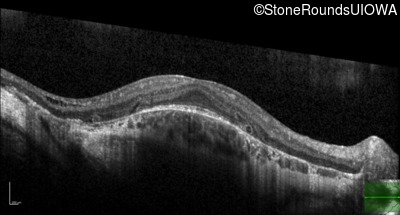

Age at visit: 36 years